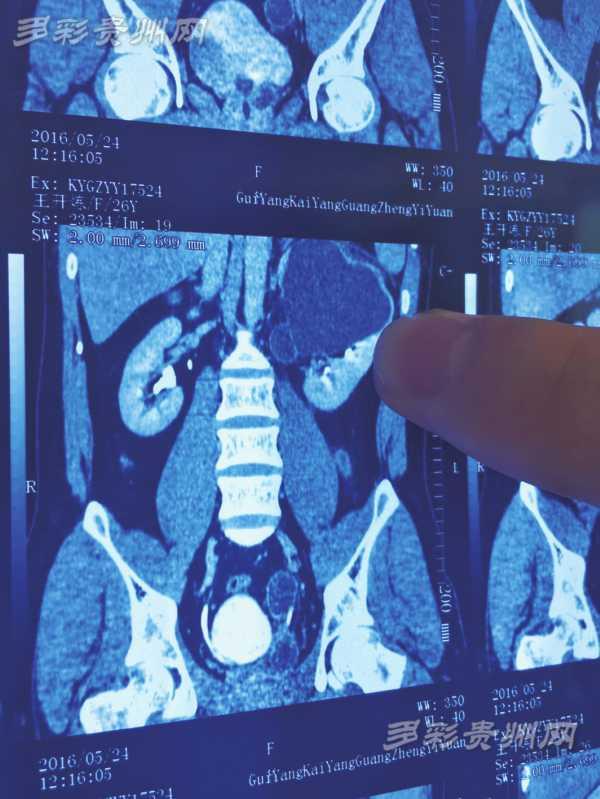

影像检查 资料显示,王开炼有4个肾,黑色阴影部分就是感染的左上肾。右边的两个肾在这份资料上已经重叠,看起来并不明显。 5小时手术成功切除1个肾 梅傲冰拿出王开炼的检查资料向记者介绍:“他的左上肾患有严重的肾积水,覆盖压迫左下肾,合并感染导致腰疼、发烧等一系列病症。”原来,王开炼4个肾每侧两个,各有一个供血系统和排尿系统,每侧的两个肾类似连体婴儿一样长在一起。“正常人的肾跟自己的拳头大小差不多,王开炼的4个肾都比正常人小,只有婴儿拳头那么大。”梅傲冰说,4个肾中,左下肾相对较小,只有正常人的三分之一那么大。 而出现病灶的肾,则是左上肾,里面有大量的积液。根据影像检查结果,积液已致这个肾变得比原来大3至5倍。“如果不及时切除左上肾,他的合并感染会更加严重,且还可能会危及到其它的肾。”梅傲冰说,好在经过半个月的治疗,王开炼的感染控制住了。在此期间,梅傲冰多次研究了手术切除方案,最后决定用最先进,也是最成熟的腹腔镜微创手术切除左上肾。 “手术是6月15日进行的。”梅傲冰介绍,病人是11点半进的手术室,经过术前麻醉等准备工作,手术在下午1点半正式开始。下午6点不到,手术完毕。“手术相当成功,基本上是零出血。”梅傲冰说,腹腔镜手术只在病人腹部开几个小孔,就成功摘除了他的左上肾。